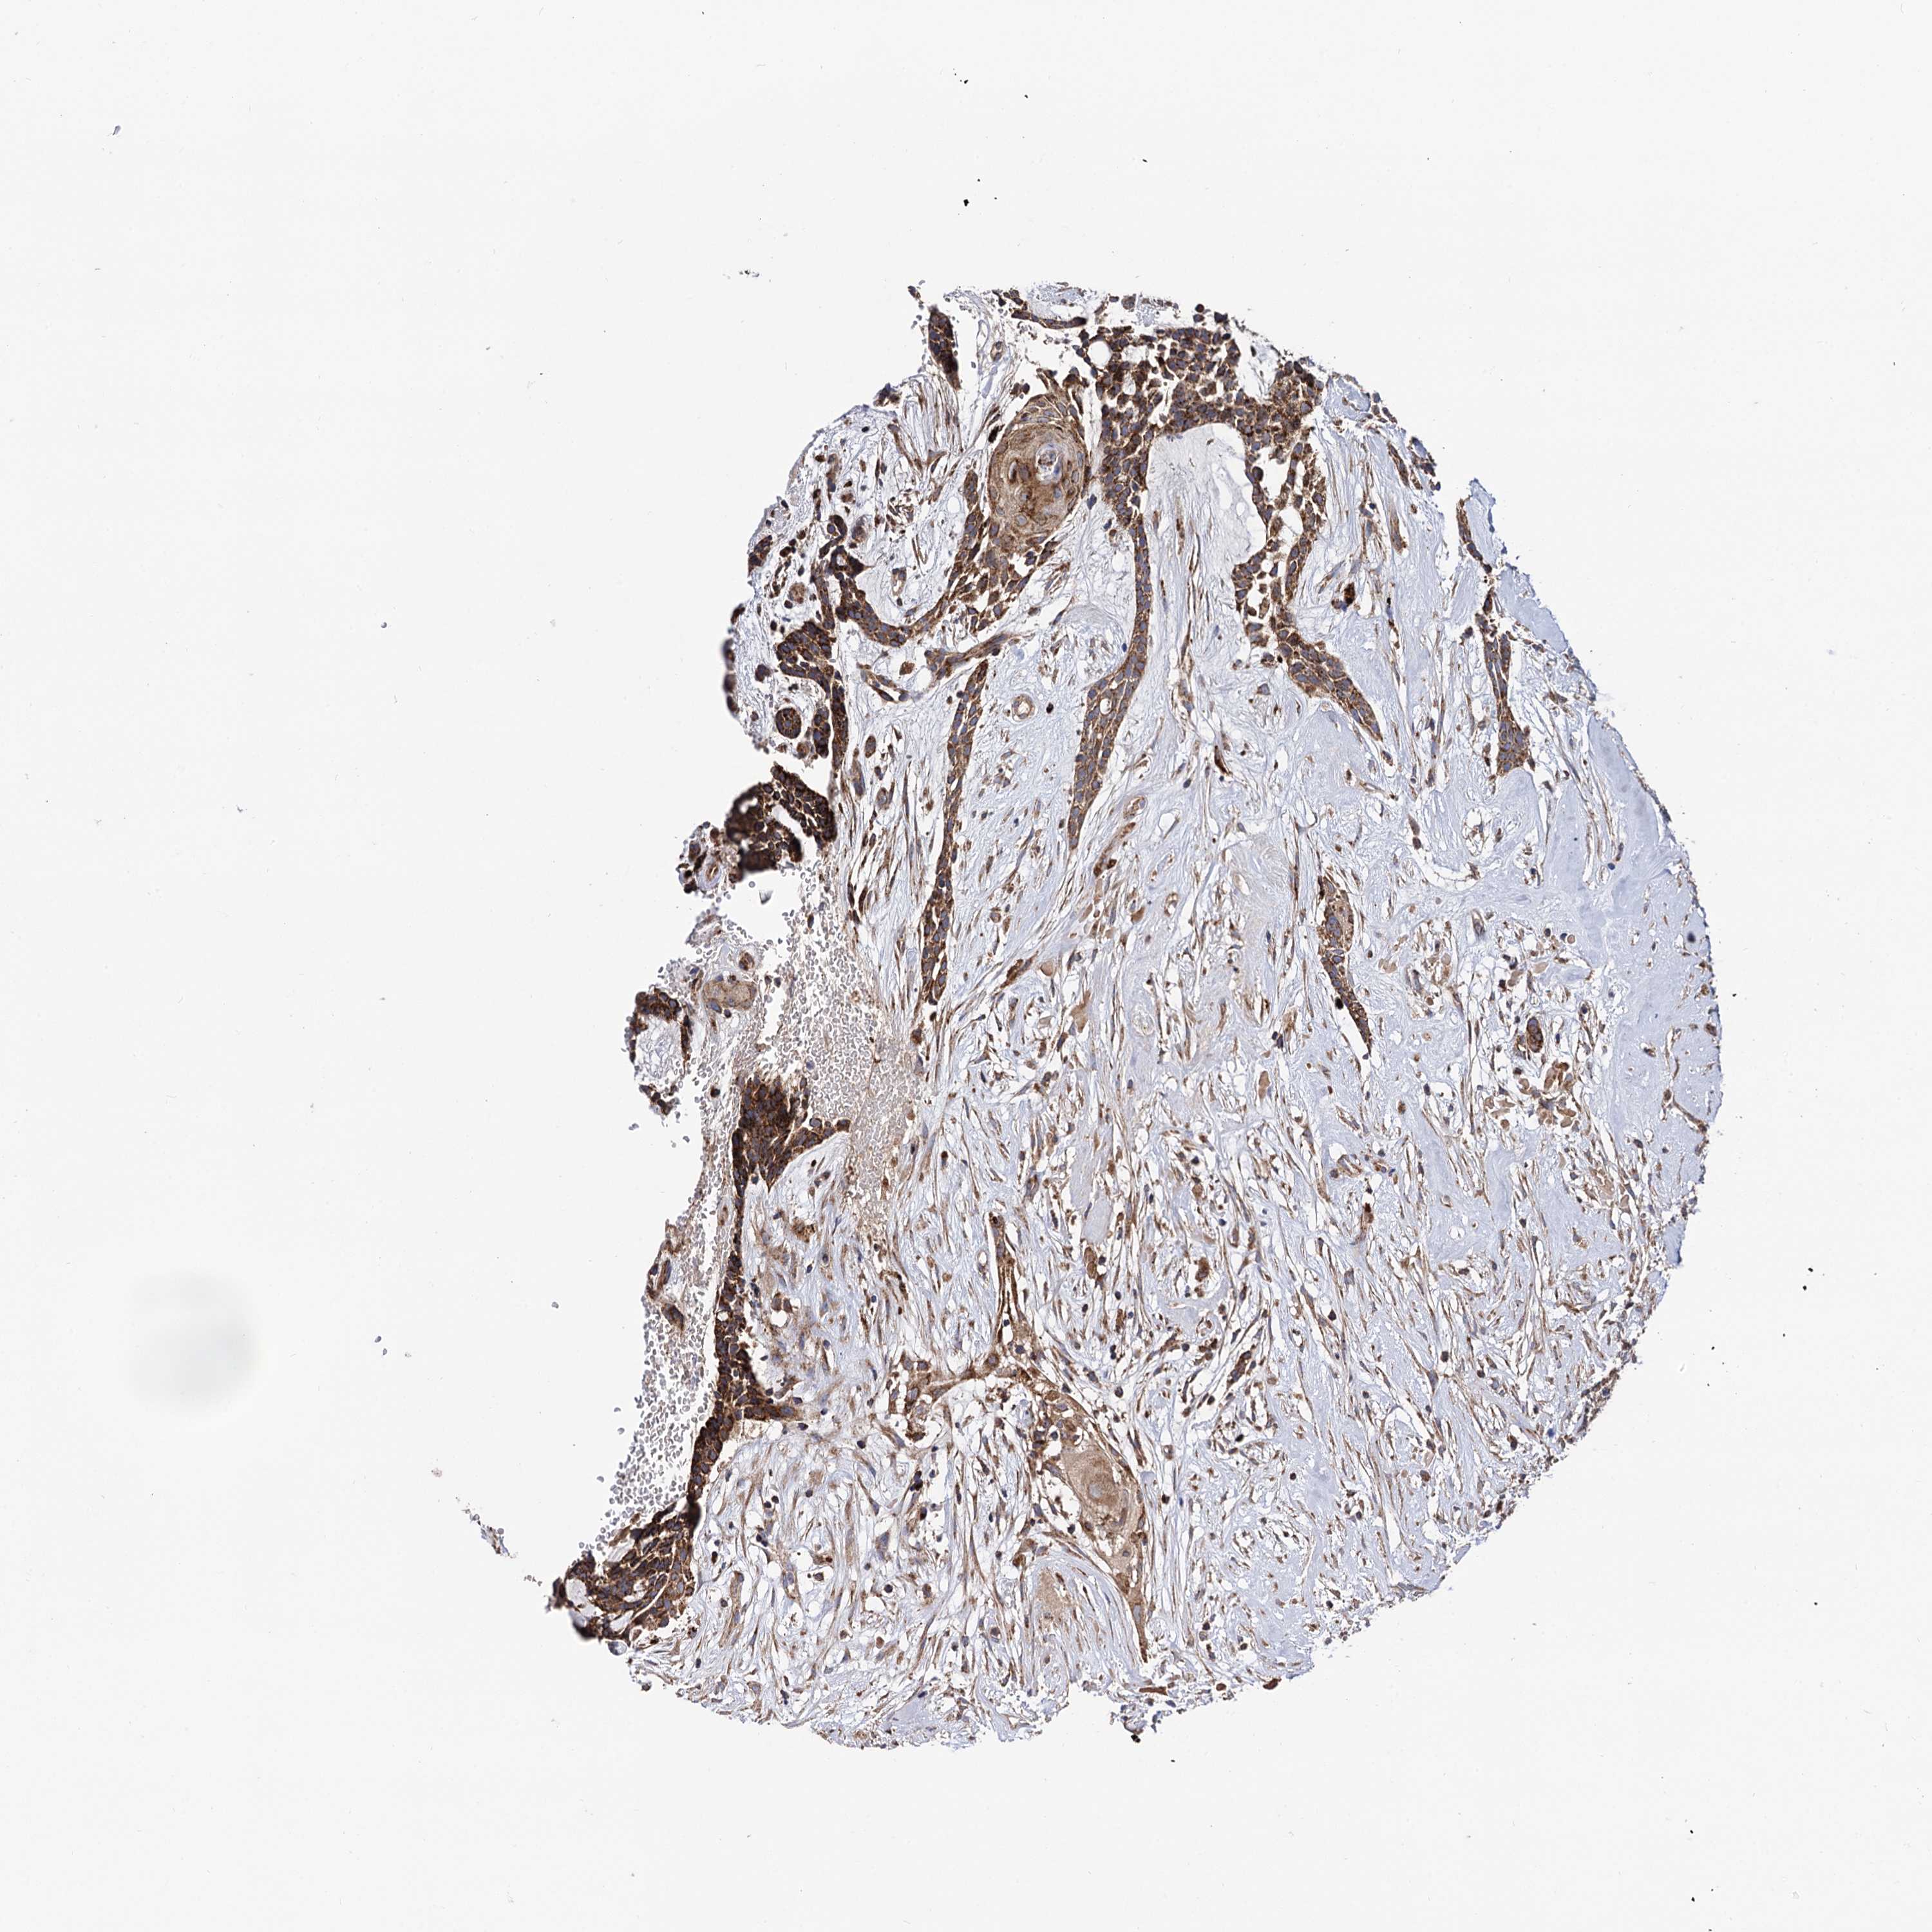

HEAD AND NECK CANCER - Protein expressioni

A mouse-over function shows sample information and annotation data. Click on an image to view it in a full screen mode. Samples can be filtered based on level of antibody staining by selecting one or several of the following categories: high, medium, low and not detected. The assay and annotation is described here.

Antibody stainingi

Antibody staining in the annotated cell types in the current human tissue is reported as not detected, low, medium, or high, based on conventional immunohistochemistry profiling in selected tissues. This score is based on the combination of the staining intensity and fraction of stained cells.

Each image is clickable and will lead to virtual microscopy that enables deeper exploration of all samples and also displays staining intensity scores, fraction scores and subcellular localization as well as patient and tissue information for each sample.

Antibody HPA040845

Staining

High

Medium

Low

Not detected

Intensity

Strong

Moderate

Weak

Negative

Quantity

>75%

75%-25%

<25%

None

Location

Nuclear

Cytoplasmic/membranous

Cytoplasmic/membranous,nuclear

Adenocarcinoma, NOS

Squamous cell carcinoma, NOS